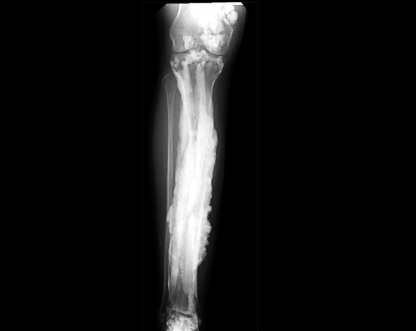

The X-ray showing periosteal lifting and _____ appearance is suggestive of osteosarcoma